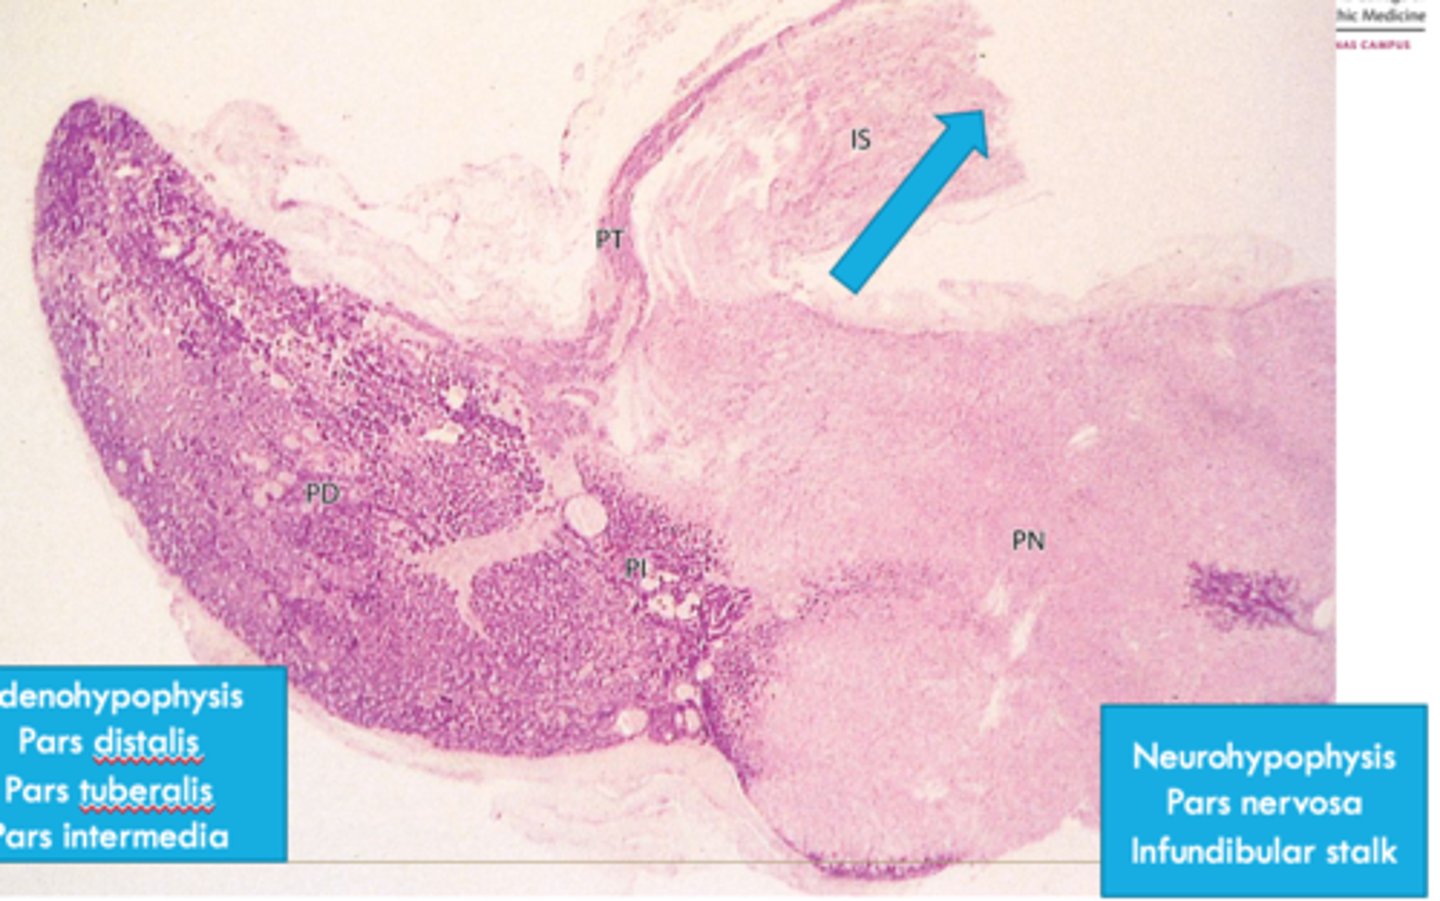

anterior

parts of the _____ pituitary:

-pars tuberalis

-pars intermedia

-pars distalis

posterior

parts of the anterior pituitary:

-infundibular stalk

-pars nervosa

neurohypophysis

origin of __________:

-bud grows down from the diencephalon as a stalk

adenohypophysis

-hypophyseal (rathke) pouch from ectoderm growing cranially

posterior pituitary is aka:

anterior pituitary is aka:

anterior pituitary

ID dark-stained tissue

posterior pituitary

ID light-stained tissue

pars intermedia

What part of the pituitary:

-posterior portion of the anterior pituitary

-in contact with neural tissue

-most active during fetal development

pars tuberalis

-part of anterior pituitary that wraps around the infundibulum

-composed of epithelial tissue within a thin wrapping of connective tissue

pars nervosa

made up of modified glial cells and axons that have descended from the hypothalamus